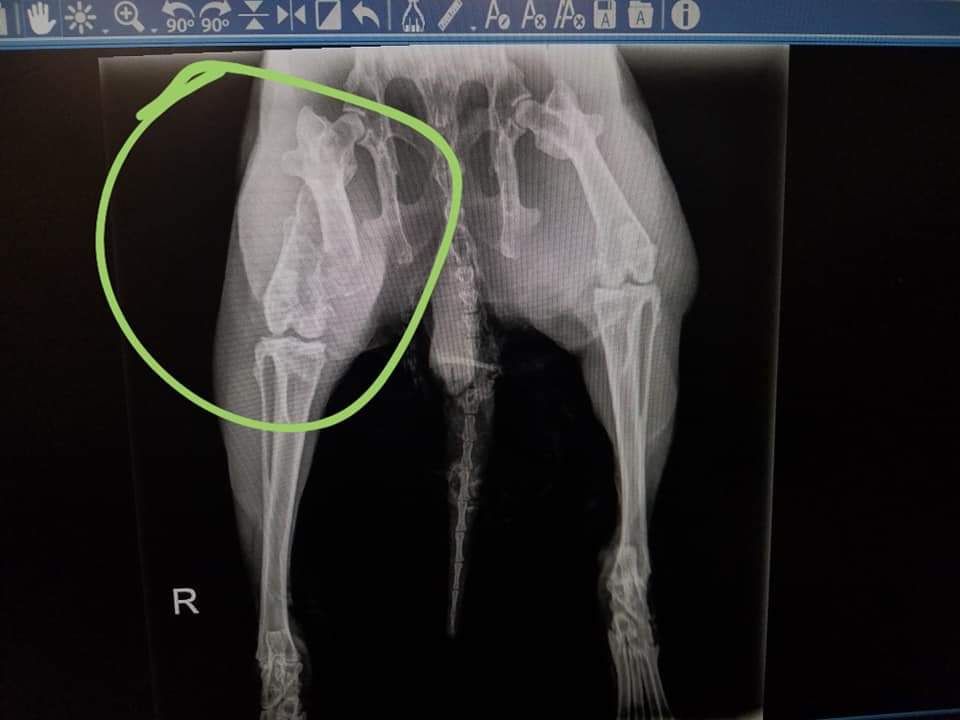

He underwent eyelid surgery to fix a genetic abnormality that was causing the eye infections, and is healing nicely. His femur appears to be an old injury that was never treated and therefore he has permanent mobility difficulty. All of his teeth are deteriorating at the root and he will need to have them removed to prevent abscesses from forming. Because the procedure is so delicate, he will undergo 4 surgeries total to remove each section.